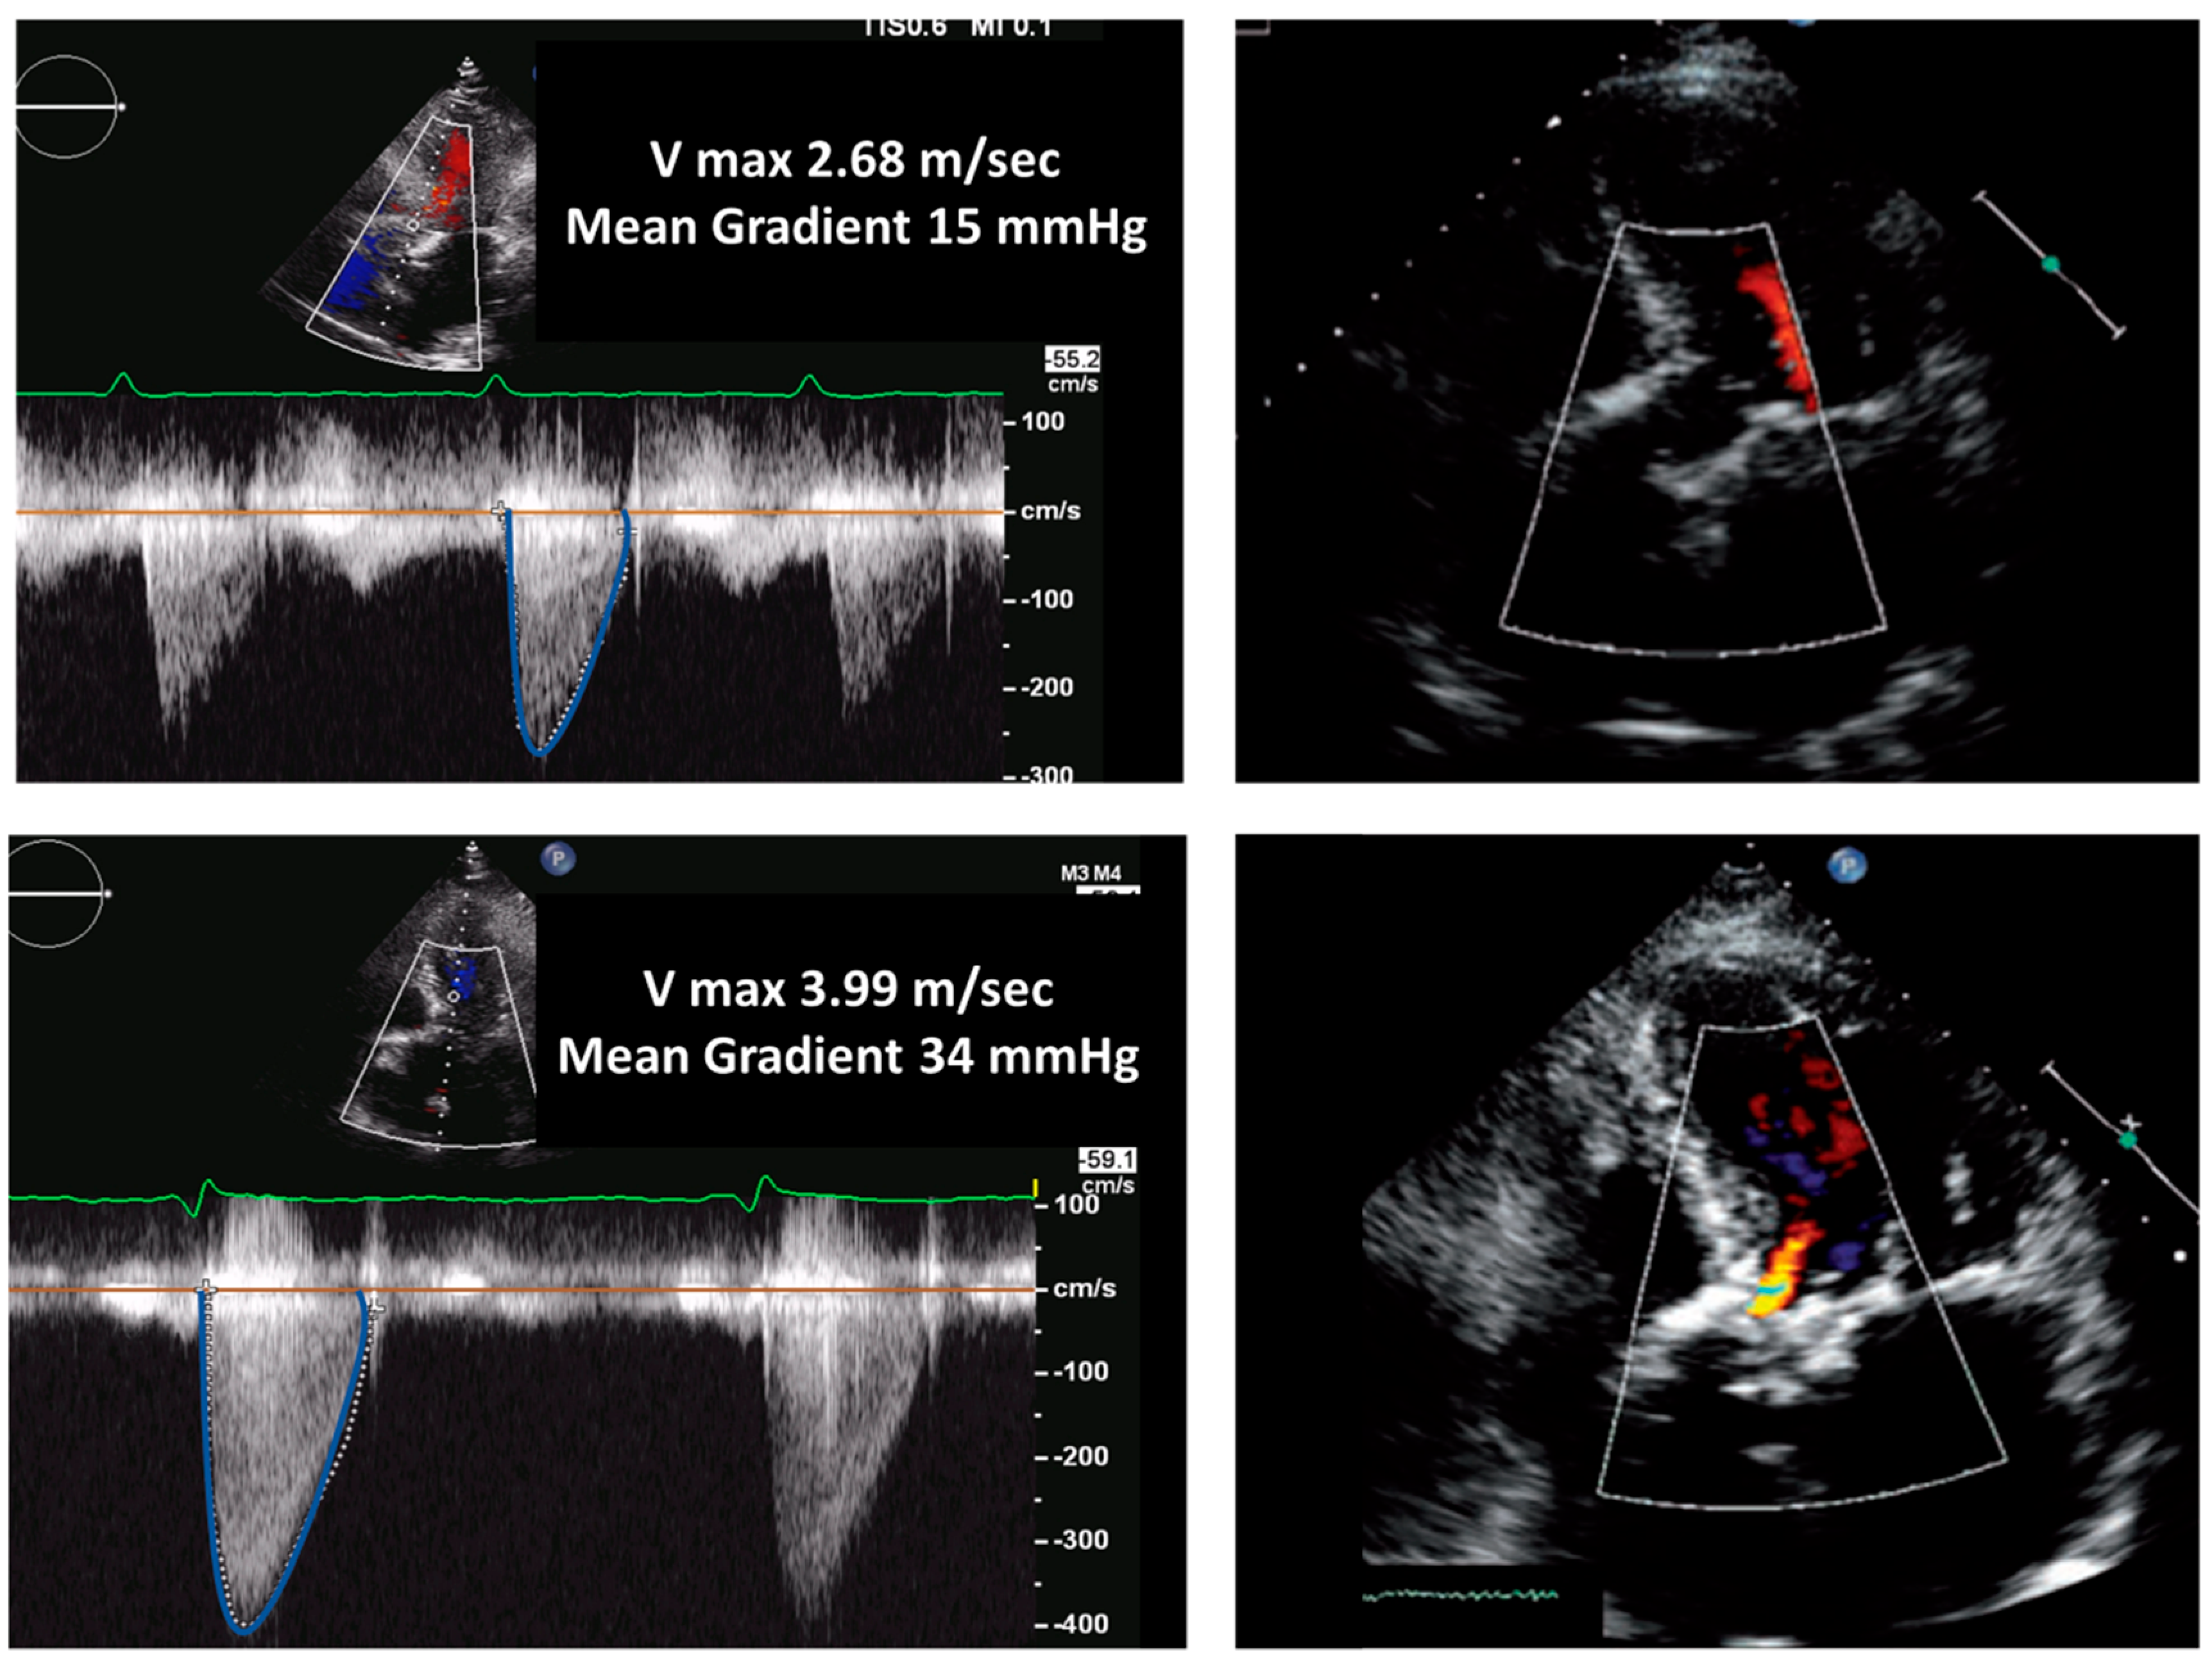

Figure 1. Biological aortic prosthesis at 1 year and 7 years after implantation. Top panels (1-year follow-up): normal gradients and normal morphology of the valve. Bottom panels (7-year follow-up): Significant increase in gradients and thickening of the valve associated with mild regurgitation; these findings are indicative of structural valve degeneration.